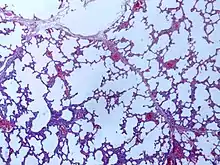

![]() | Emphysema | Micrograph of empysema lung showing dialated, large alveoli separated by thin septa. Some septae are ruptured and appear to be floating in the alveloar spaces. Grossly emphysematous lung appears pale and voluminous. | Category: Histopathology of pulmonary emphysema | Emphysema |